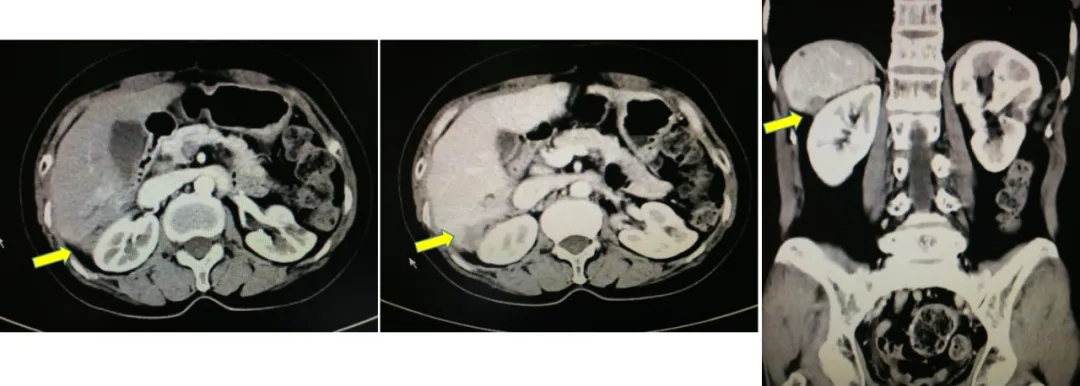

2021.5.8 PET-CT:肝肾隐窝转移灶。2021.5.12复查CA125水平为95.5U/ml。

PET-CT检查结果